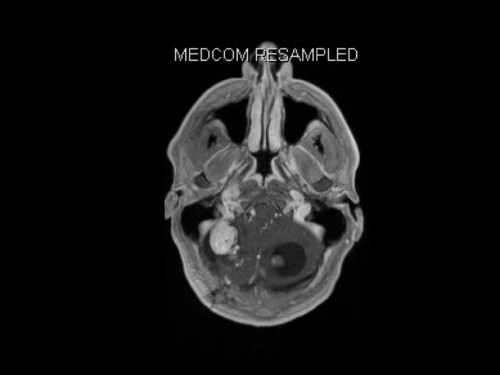

19-jähriger Mann. Er klagt seit mehreren Wochen über Schwindel und Kopfschmerzen. Im Alter von 16 Jahren sind er und sein Zwillingsbruder an einem Phäochromozytom operiert worden.